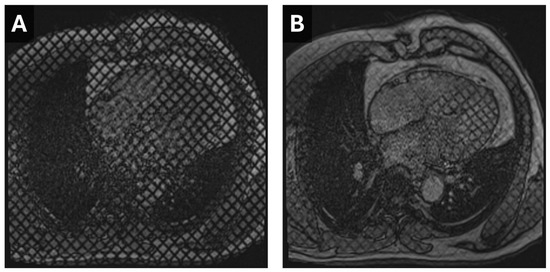

Cardiac CT is well-suited for the evaluation of morphologic features, such as wall thickness and chamber dimensions, given its excellent spatial resolution and volumetric acquisition. It is worth noting that most CT coronary angiography is performed during end-systole or mid-diastole, which may result in an overestimation of wall thickness and underestimate end-diastolic volumes []. Additional features, such as atrial wall thickening, left ventricular thrombus, or non-compaction, can be identified regardless of the cardiac cycle phase (Figure 1) []. Thrombus detection, in particular, is often more reliable with CT than echocardiography, as it appears as a filling defect in a contrast-filled chamber. Beyond cardiac morphology, CT can reveal extracardiac findings that may provide broader diagnostic insights. For instance, bilateral hilar adenopathy, visible on cardiac CT, may suggest sarcoidosis, expanding the diagnostic perspective beyond cardiac pathology (Figure 2).

Figure 2. Sarcoidosis in CT Cardiac Imaging. CMR short-axis delayed-enhanced inversion recovery image through the LV base (A) from a patient with complete heart block and sarcoidosis with myocardial involvement. There is nonvascular delayed enhancement in the basilar septum (arrow). A contrast-enhanced cardiac CT from the same patient demonstrates a correlating area of decreased myocardial perfusion ((B), arrow). Axial reconstruction from the same CT (C) demonstrates partially calcified mediastinal and hilar lymphadenopathy (arrowheads) consistent with adenopathy in the setting of sarcoidosis.